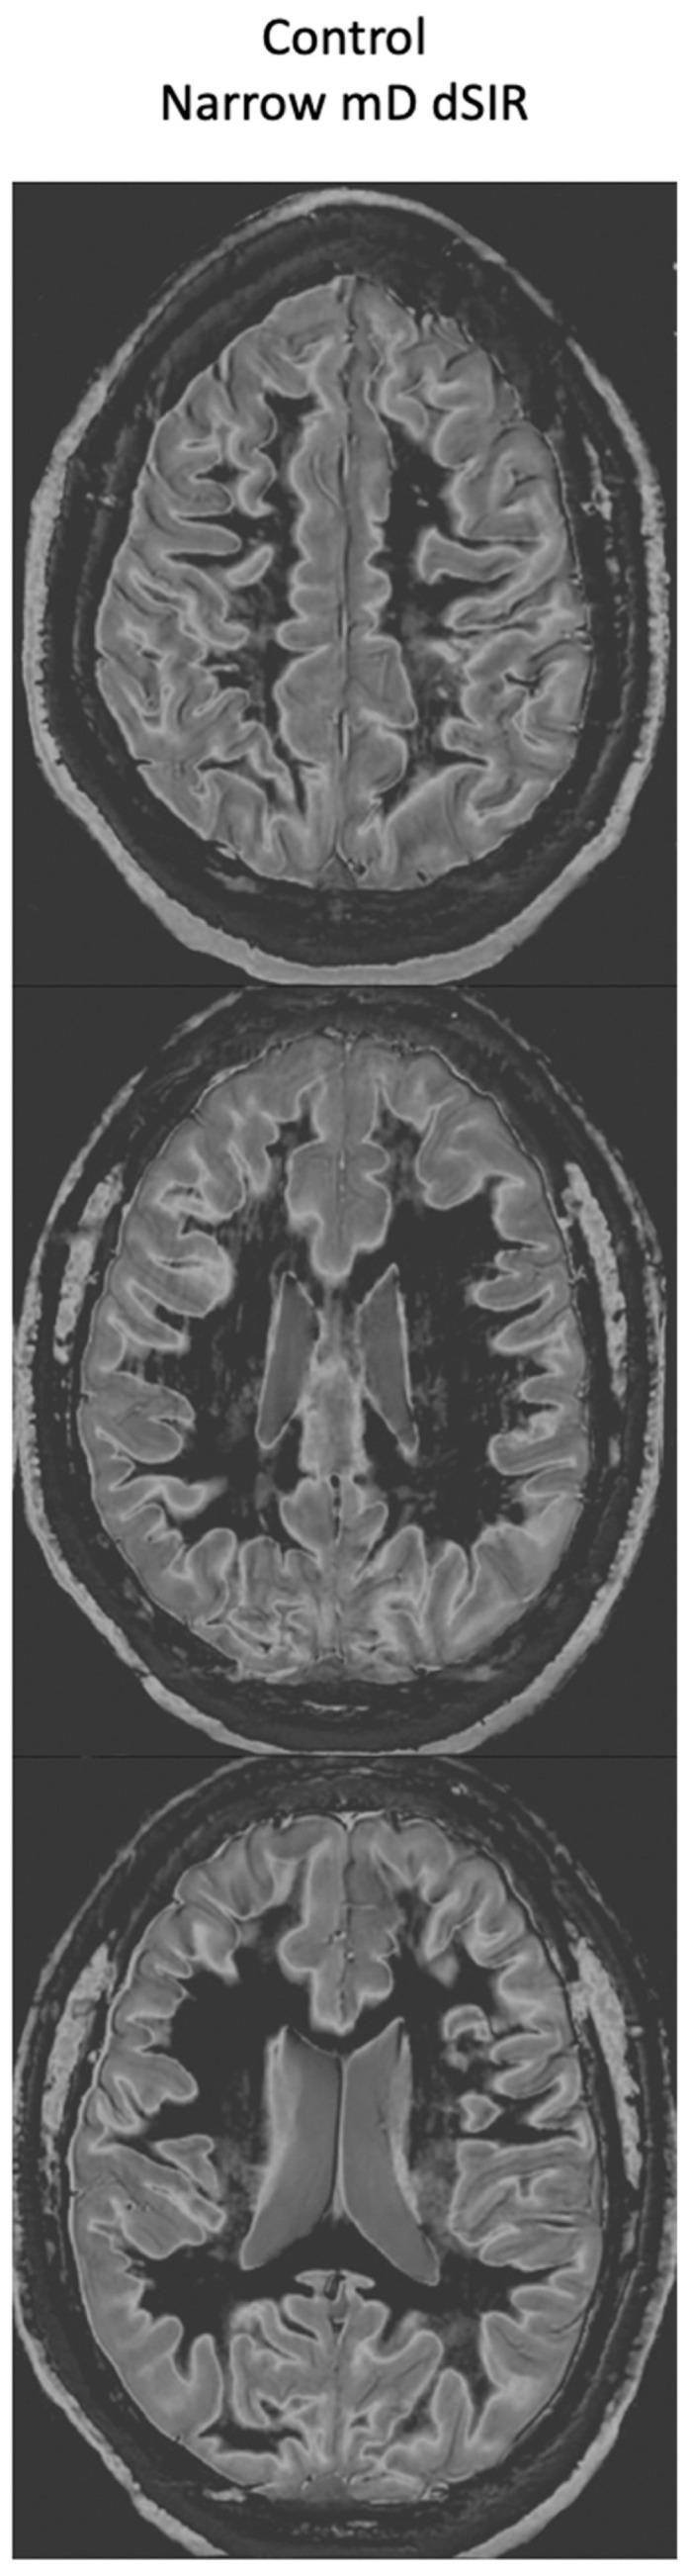

Ultra-high contrast (UHC) MRI describes forms of MRI in which little or no contrast is seen on conventional MRI images but very high contrast is seen with UHC techniques. One of these techniques uses the divided subtracted inversion recovery (dSIR) sequence, which, in modelling studies, can produce ten times the contrast of conventional inversion recovery (IR) sequences. When used in cases of mild traumatic brain injury (mTBI), the dSIR sequence frequently shows extensive abnormalities in white matter that appears normal when imaged with conventional T-fluid-attenuated IR (T-FLAIR) sequences. The changes are bilateral and symmetrical in white matter of the cerebral and cerebellar hemispheres. They partially spare the anterior and posterior central corpus callosum and peripheral white matter of the cerebral hemispheres and are described as the whiteout sign. In addition to mTBI, the whiteout sign has also been seen in methamphetamine use disorder and Grinker's myelinopathy (delayed post-hypoxic leukoencephalopathy) in the absence of abnormalities on T-FLAIR images, and is a central component of post-insult leukoencephalopathy syndromes. This paper describes the concept of ultra-high contrast MRI, the whiteout sign, the theory underlying the use of dSIR sequences and post-insult leukoencephalopathy syndromes.

超高对比(UHC)MRI 描述了这样一些 MRI 形式,在常规 MRI 图像上几乎没有或没有对比,但在 UHC 技术中可以看到非常高的对比。其中一种技术使用分裂相减反转恢复(dSIR)序列,在建模研究中,该序列可以产生比常规反转恢复(IR)序列高十倍的对比度。当用于轻度创伤性脑损伤(mTBI)时,dSIR 序列经常在白质中显示出广泛的异常,而在使用常规 T 液衰减反转恢复(T-FLAIR)序列成像时,白质看起来正常。这些变化在大脑和小脑半球的白质中是双侧对称的。它们部分保留了前中央和后中央胼胝体以及大脑半球的外周白质,被描述为“白化征”。除了 mTBI 之外,在没有 T-FLAIR 图像异常的情况下,该白化征也出现在苯丙胺使用障碍和 Grinker 髓鞘病(缺氧后迟发性白质脑病)中,是创伤后白质脑病综合征的一个核心组成部分。本文描述了超高对比 MRI、白化征、dSIR 序列使用的理论以及创伤后白质脑病综合征的概念。